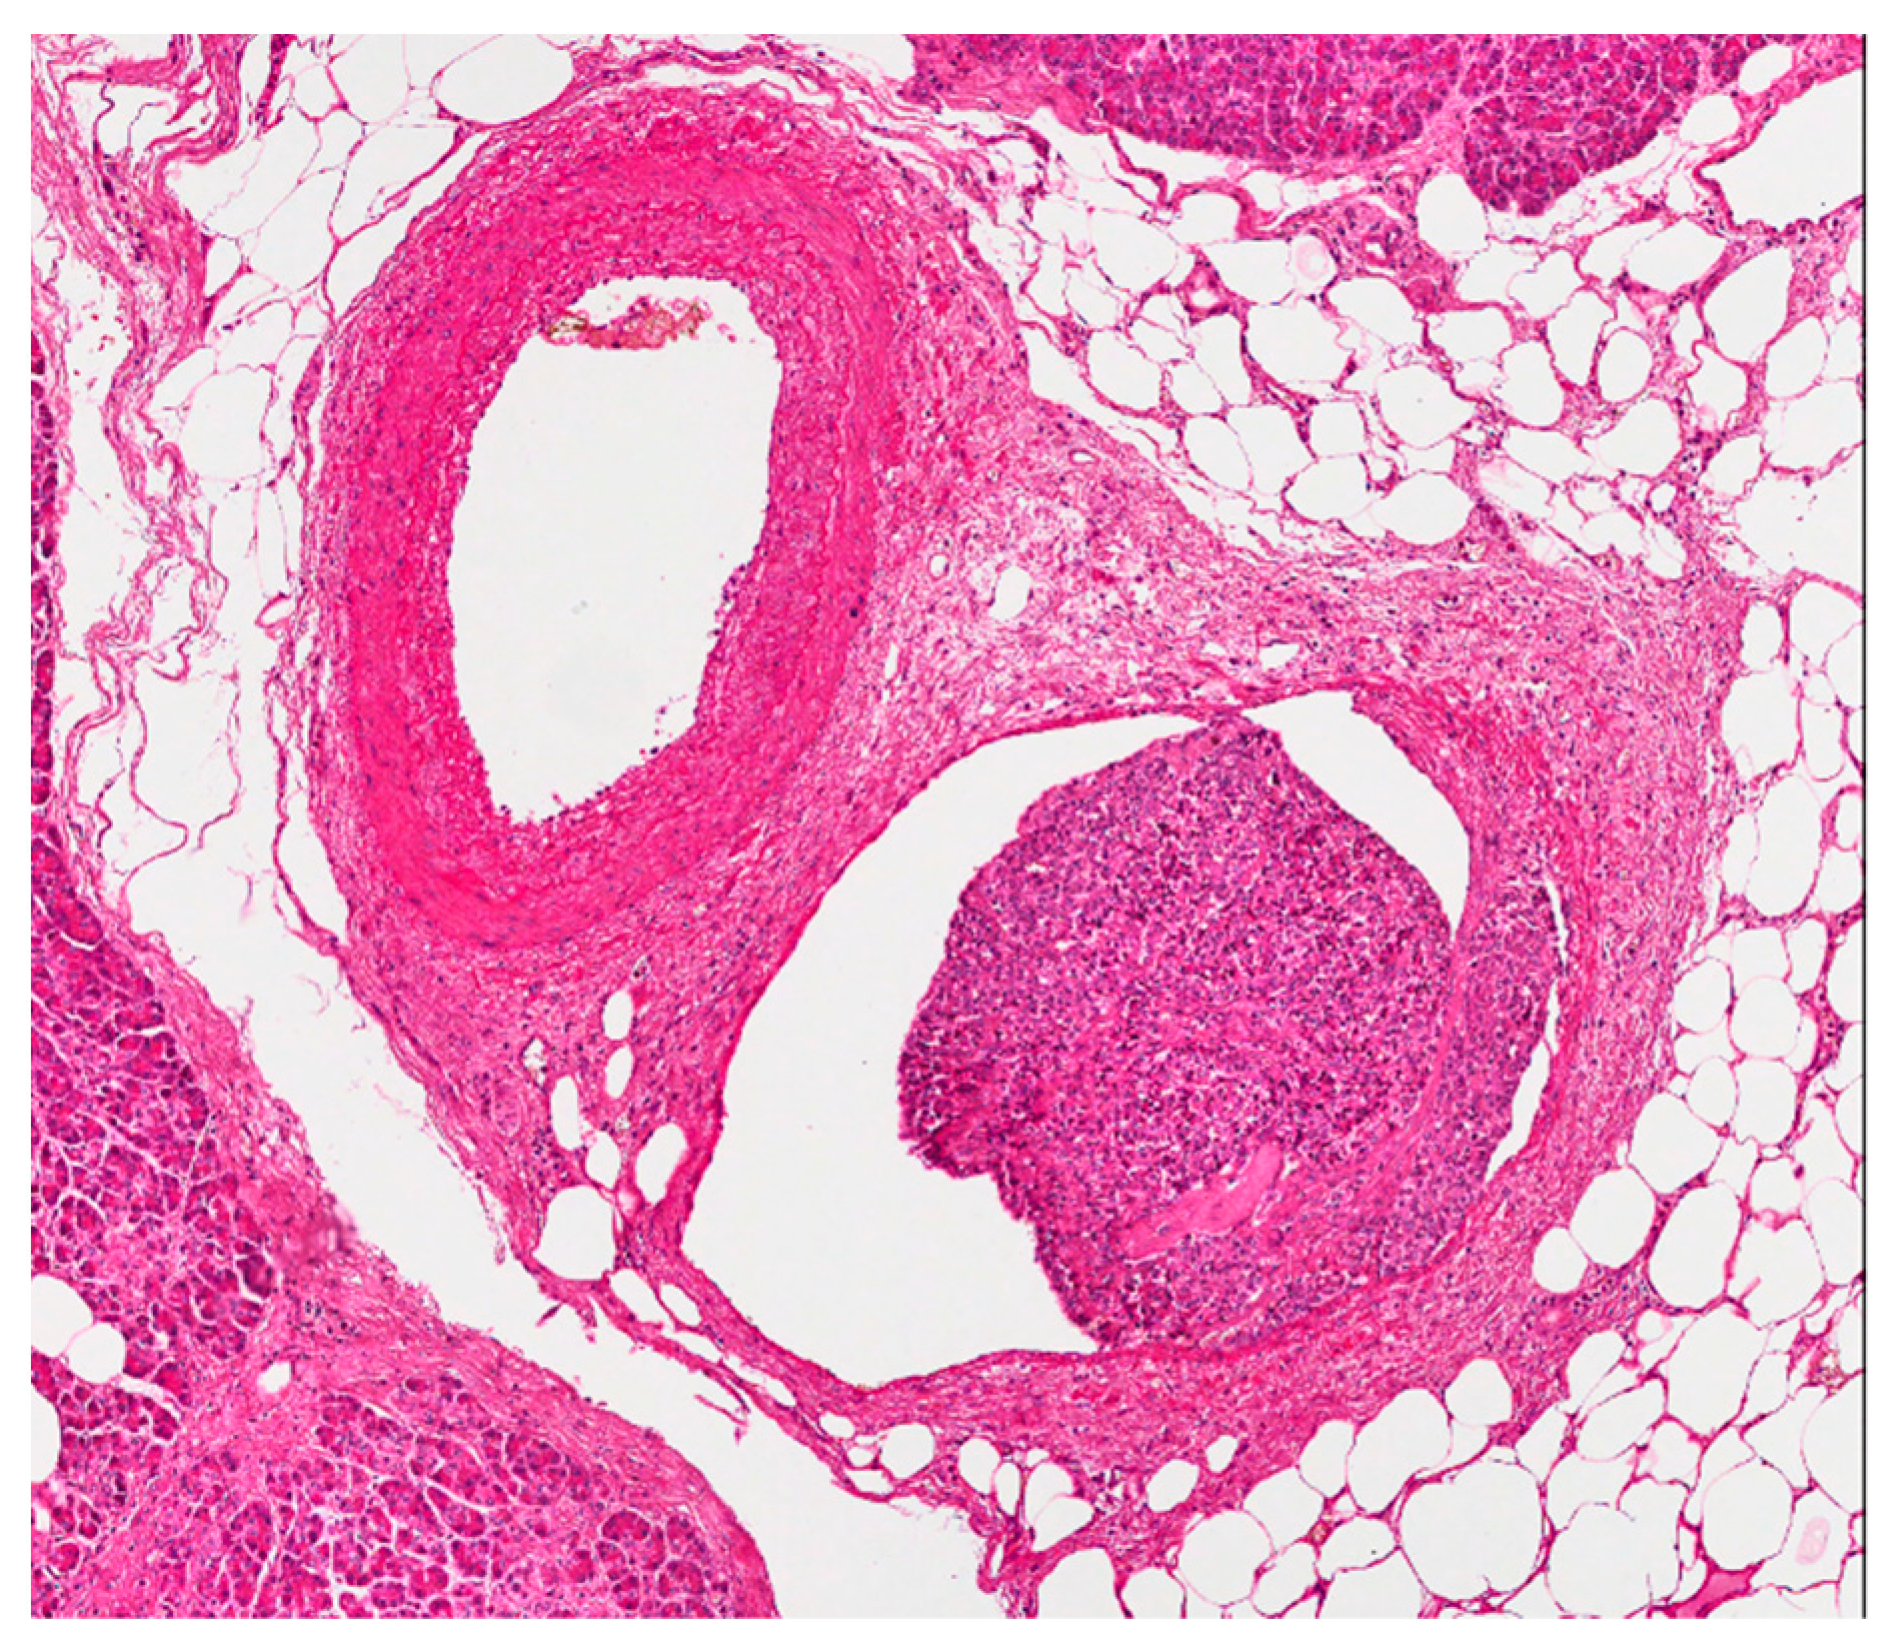

Figure 3.

In paired vessels, neoplastic thrombus is seen in the venula (in the middle of the picture). The patient is the same of Figure 2 (hematoxylin eosin stain; 100×).